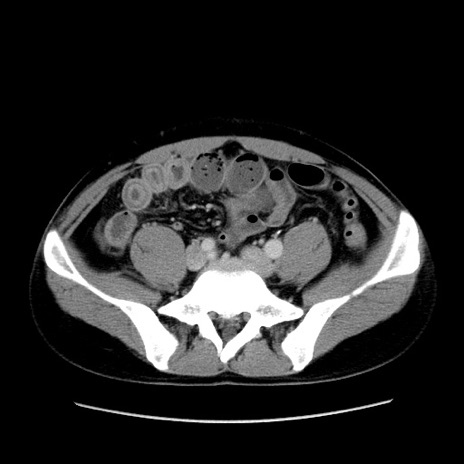

症例4(横断像)

【症例】30歳代男性

【主訴】腹痛、嘔吐

【現病歴】昨晩から突然の腹痛あり、その後嘔吐、軟便も出現。腹痛が改善しないため救急搬送となる。2日前にしめ鯖の食事歴あり。

【身体所見】意識清明、苦悶様、BP 135/90mmHg、BT 35.7℃、腹部:平坦、やや硬、心窩部〜臍部に自発痛、圧痛あり、筋性防御+、反跳痛-

【データ】WBC 8100、CRP 0.57